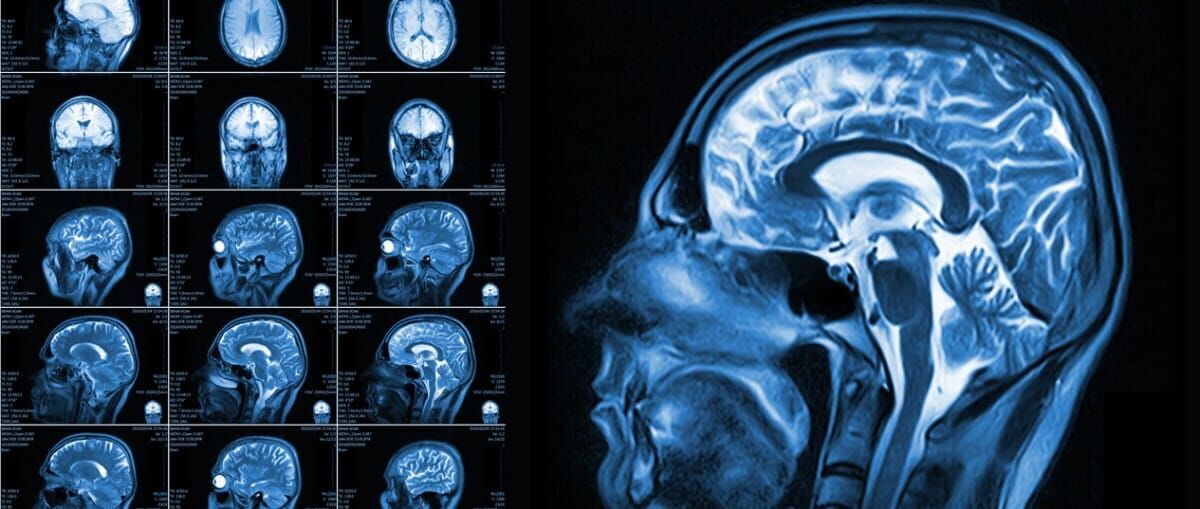

How are traumatic brain injuries diagnosed?

Medical professionals use several methods to determine the severity of a TBI. One method is the neurological evaluation, where a neurologist checks the patient’s memory, motor function skills, and sensory functions. Another method is an imaging test. Medical professionals will use a CT scan or MRI to search for any signs of brain bleeding or swelling of the brain. The last method used is the blood test, where a medical professional will use the Banyan Brain Trauma Indicator (BTI) to search for proteins in the blood. This is a sign that indicates the presence of a concussion or traumatic brain injury.